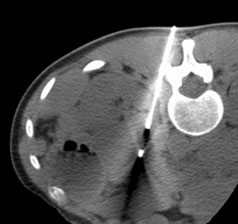

画像ガイド下生検

CT、X線透視、超音波、MRIを用いて、体幹部、四肢の腫瘍の組織を診断するため針を刺して組織を採取するものです。基本的に、体幹部、四肢であればほぼすべての部位の腫瘍に対し可能です。

図1 縦隔腫瘍に対するCTガイド下針生検

CTで血管など他臓器と腫瘍の位置関係を確認しつつ針を刺入することで、安全に生検を施行することが可能となります。

図2 左副腎腫瘍に対するCTガイド下針生検

体の深部にある病変でも、CTガイド下に針を刺入することで、安全かつ確実に生検が施行できます。